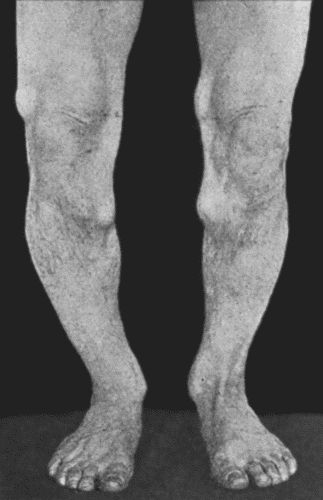

67.Extensive Varix of Internal Saphena System on Left Leg 291

164.Charcot's Disease of both Ankles: front view 535

165.Charcot's Disease of both Ankles: back view 536